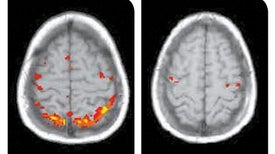

Dancing, rowing and even finger tapping in unison unleash powerful forces in the brain that drive good feelings